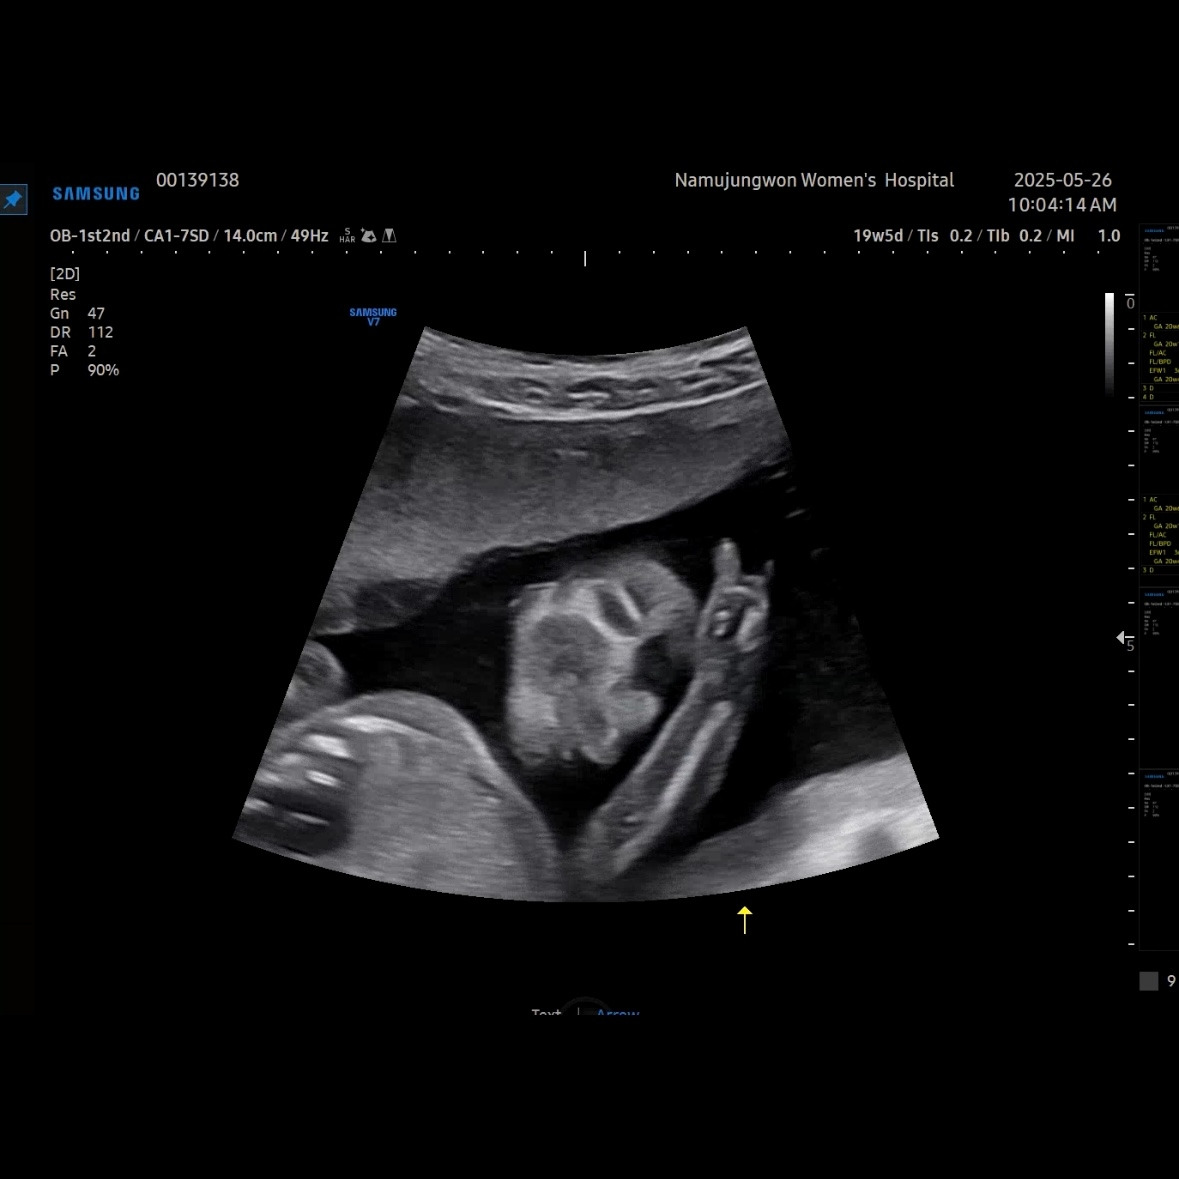

이제 얼굴이 형태가 많이 보인다. 코랑 입 위주로 보여줬다. 눈 쪽으로는 손을 올리고 있었다. 이렇게 보면 장기나 뇌나 얼굴이나 대부분 만들어져서 꽤 클 것 같이 생각되지만, 아직까지 400g이 안 되는 무게였다.

오늘로 23주 차 500g 정도로 늘었을 것이라고 한다. 다음 주에 유민이 보러 가는 날이 기다려진다. 정밀 초음파에서 얼굴도 잘 보여주기를.

한 일주일 전부터 태동이 잘 느껴진다. 잠을 못 자고 할 정도는 아니고 배안에서 귀엽게 쿡쿡 찔러댄다. 오늘은 딸꾹질 같은 것도 느껴졌다.